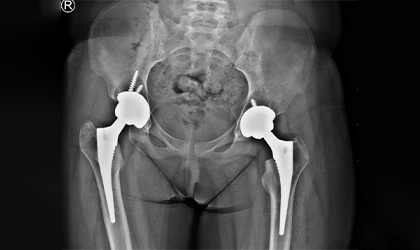

Bilateral Hip Recovery

This 34 year old medical representative had avascular necrosis with collapse of both her hips